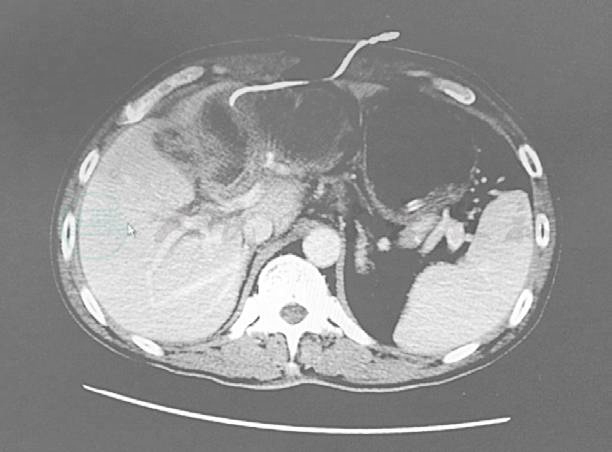

患者术后4日通气,给予糖盐水空肠造瘘管注入;术后第5日给予肠内营养液支持,每日复查腹腔引流液淀粉酶和血淀粉酶均正常。术后7日拔出胃管,给予流质饮食。术后第9日出现恶心呕吐,呕吐物为墨绿色胃液,考虑胃排空障碍,予以胃肠减压,浓盐水洗胃,红霉素、多潘立酮促进胃动力,排空障碍逐步好转,并予以每日1500ml的肠内营养支持治疗。术后10日出现发热,体温38.2℃,血常规:WBC 9.46×109/L,中性粒细胞比值87.3%,CRP 103.94mg/L,查胆汁和腹腔引流液培养提示阴沟肠杆菌,对头孢类和哌拉西林/他唑巴坦等均敏感。腹腔引流液淀粉酶正常,无异常消化液引出,复查B超和CT未见腹腔内明显积液(图3、图4)。考虑无消化道瘘出现。考虑发热原因为胆道感染和腹腔感染。

图3 手术后复查的CT图像